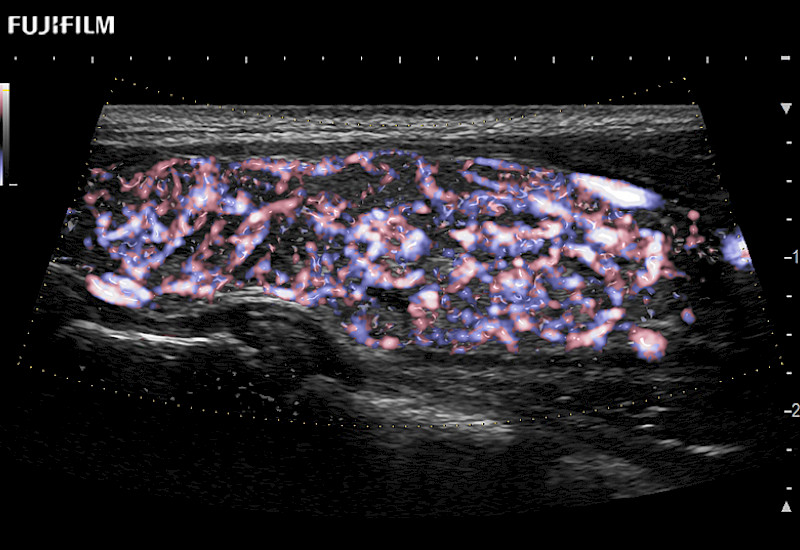

Fujifilm Healthcare understands that Surgical Oncologists demand excellence in their operating rooms — from their staff and the equipment they depend on. Fujifilm Healthcare's dedication to Surgical Oncologists provides outstanding ultrasound technology, professional support and the specialized tools necessary to best perform comprehensive real-time ultrasound imaging.

For precise surgical oncology ultrasound imaging, Fujifilm Healthcare offers premium level solutions that include:

Our dedication to Surgical Oncology allows us to offer superior image quality, outstanding system reliability and intuitive use of cutting edge technology.